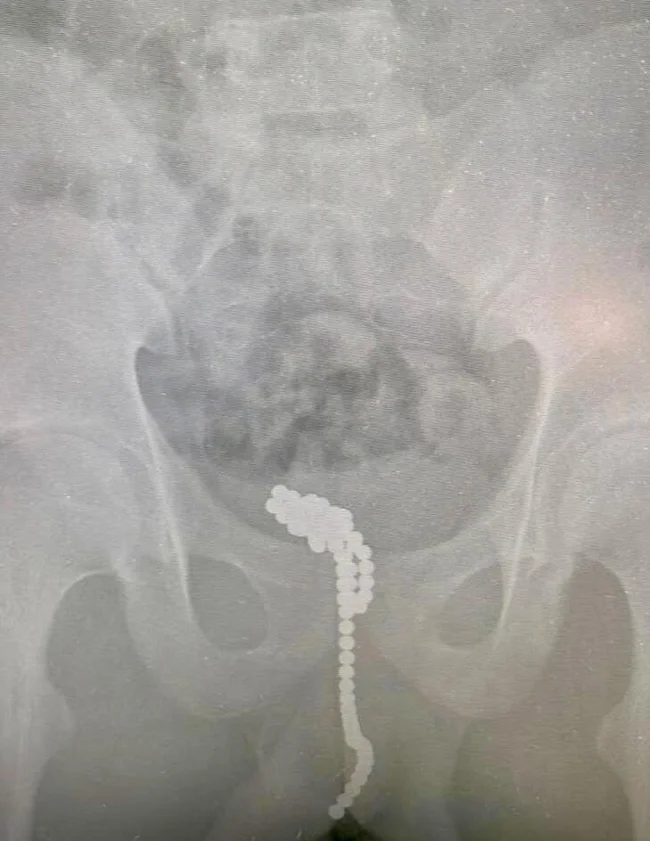

Подростковый возраст - самый опасный в жизни мальчиков. Дури много, а вот с умением думать, прежде чем делать - беда. 13-летний тинейджер из Люберец запихнул в уретру 30 магнитных шариков. Само собой, они склеились в длинную цепочку и закупорили проток. Мальчик не смог пописать, и долго терпел, а когда стало невмоготу, обратился за помощью к врачам.

Т.к. мочевой пузырь мог лопнуть от переполнения, ребёнку поставили катетер, пока готовили к операции. Через надрез на половом органе хирурги достали магнитные шарики, и на повторном рентгене проверили, чтобы внутри не осталось магнитов.